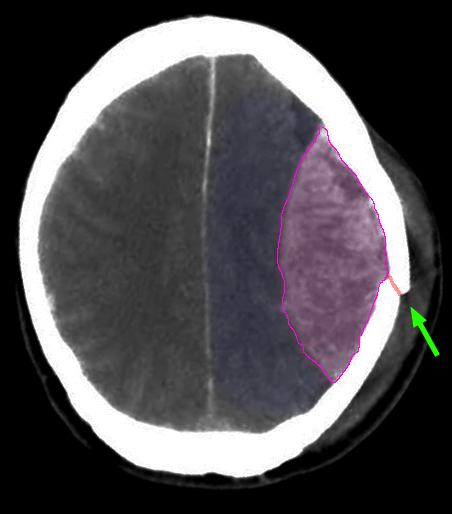

Επισκληρίδιο αιμάτωμα εγκεφάλου αριστερά. Κάταγμα κρανίου με πράσινο βέλος. |